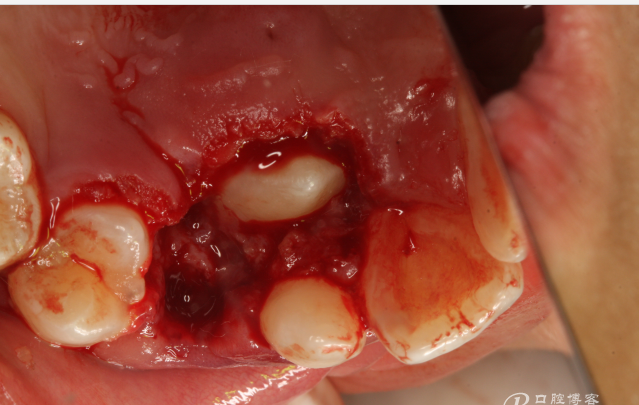

圖7.局部麻醉下、電刀切除覆蓋在13上的腭側(cè)粘膜組織。

圖8.繼續(xù)電刀切除腭側(cè)粘膜組織

圖9.清理切除部分腭側(cè)組織后的13牙冠。